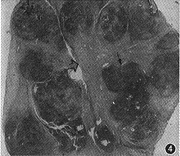

1.肿瘤CT增强影像表现特殊,可分为以下几类:(1)低密度区中伴团状高密度改变24个(图1),病理改变为在比较广泛分布的疏细胞区(Antoni B区)组织中,有相对集中分布的富细胞区(Antoni A区)(图2)。(2)弥漫点状改变20个,点状大小从1~4 mm不等,其密度不等。高密度CT值为60~80 HU,低密度为40~45 HU,两者CT值相差约20 HU。其中呈低密度点状4个;高密度点状4个;高、低密度混杂点状12个(图3)。此20个肿瘤中8个伴有1~2个形态不规则的低密度裂隙样变。高低密度混杂点状分布的病理改变为的Antoni A区、Antoni B区相互交错,分布均匀(图4)。低密度点状改变为比较广泛分布的Antoni A区或胶原基础上出现的零星分布的Antoni B区或微囊集中处,Antomi B区或微囊分布较集中时,即表现为低密度裂隙样改变。较广泛分布的Antoni B区伴少量Antoni A区或胶原则呈高密度点状改变。(3)低密度环伴中央弥漫不同密度点状改变5个,其中单纯为低密度点状或单纯为高密度点状各1个。此低密度环在病理上由Antoni B区组成。(4)中央低密度伴有环形改变8个(图5),环壁厚,环表现各异,其中表现为高、低密度混杂点状分布的3个,单纯低密度点状或高密度点状各2个,环与肌肉呈等密度1个。肿瘤中央的低密度区病理上由Antoni B集中区和(或)陈旧性出血区组成。(5)密度均匀的12个肿瘤中,等密度与低密度各5个,囊性变2个。在病理上等密度多由Antoni A区及胶原组成,Antoni B区较少,分散在Antoni A区及胶原间;而低密度肿瘤(图6)为均匀一致的Antoni B区及部分陈旧性出血组成,几乎无Antoni A区细胞(图7)。囊性肿瘤巨检时见黄色液体流出,囊壁上仍见典型Antoni A、Antoni B区改变。(6)增强特别明显的肿瘤3个,其中2个为弥漫点状改变(图8),1个为厚环。病理显示此3个肿瘤由丰富的Antoni A区组成,夹杂有微囊,而Antoni B区少见(图9),其中仅2个血供比较丰富。

图4 图3肿瘤相应切面组织学表现。Antoni A区及Antoni B区相互交错分布。黑箭示Antoni A区;空箭示Antoni B区